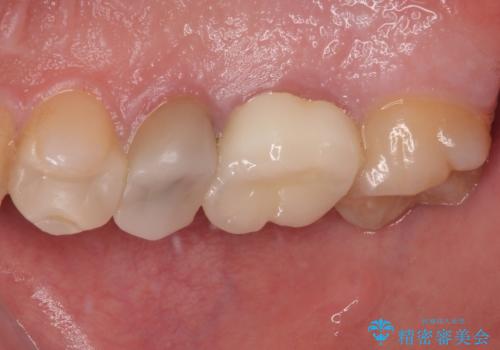

見た目、機能面ともに満足していただけました。

咬み合わせが強く以前のセラミックを割ってしまっているので就寝時にはナイトガードを使ってもらう予定です。

今後もメンテナンスで通っていただきながら、経過観察していく予定です。